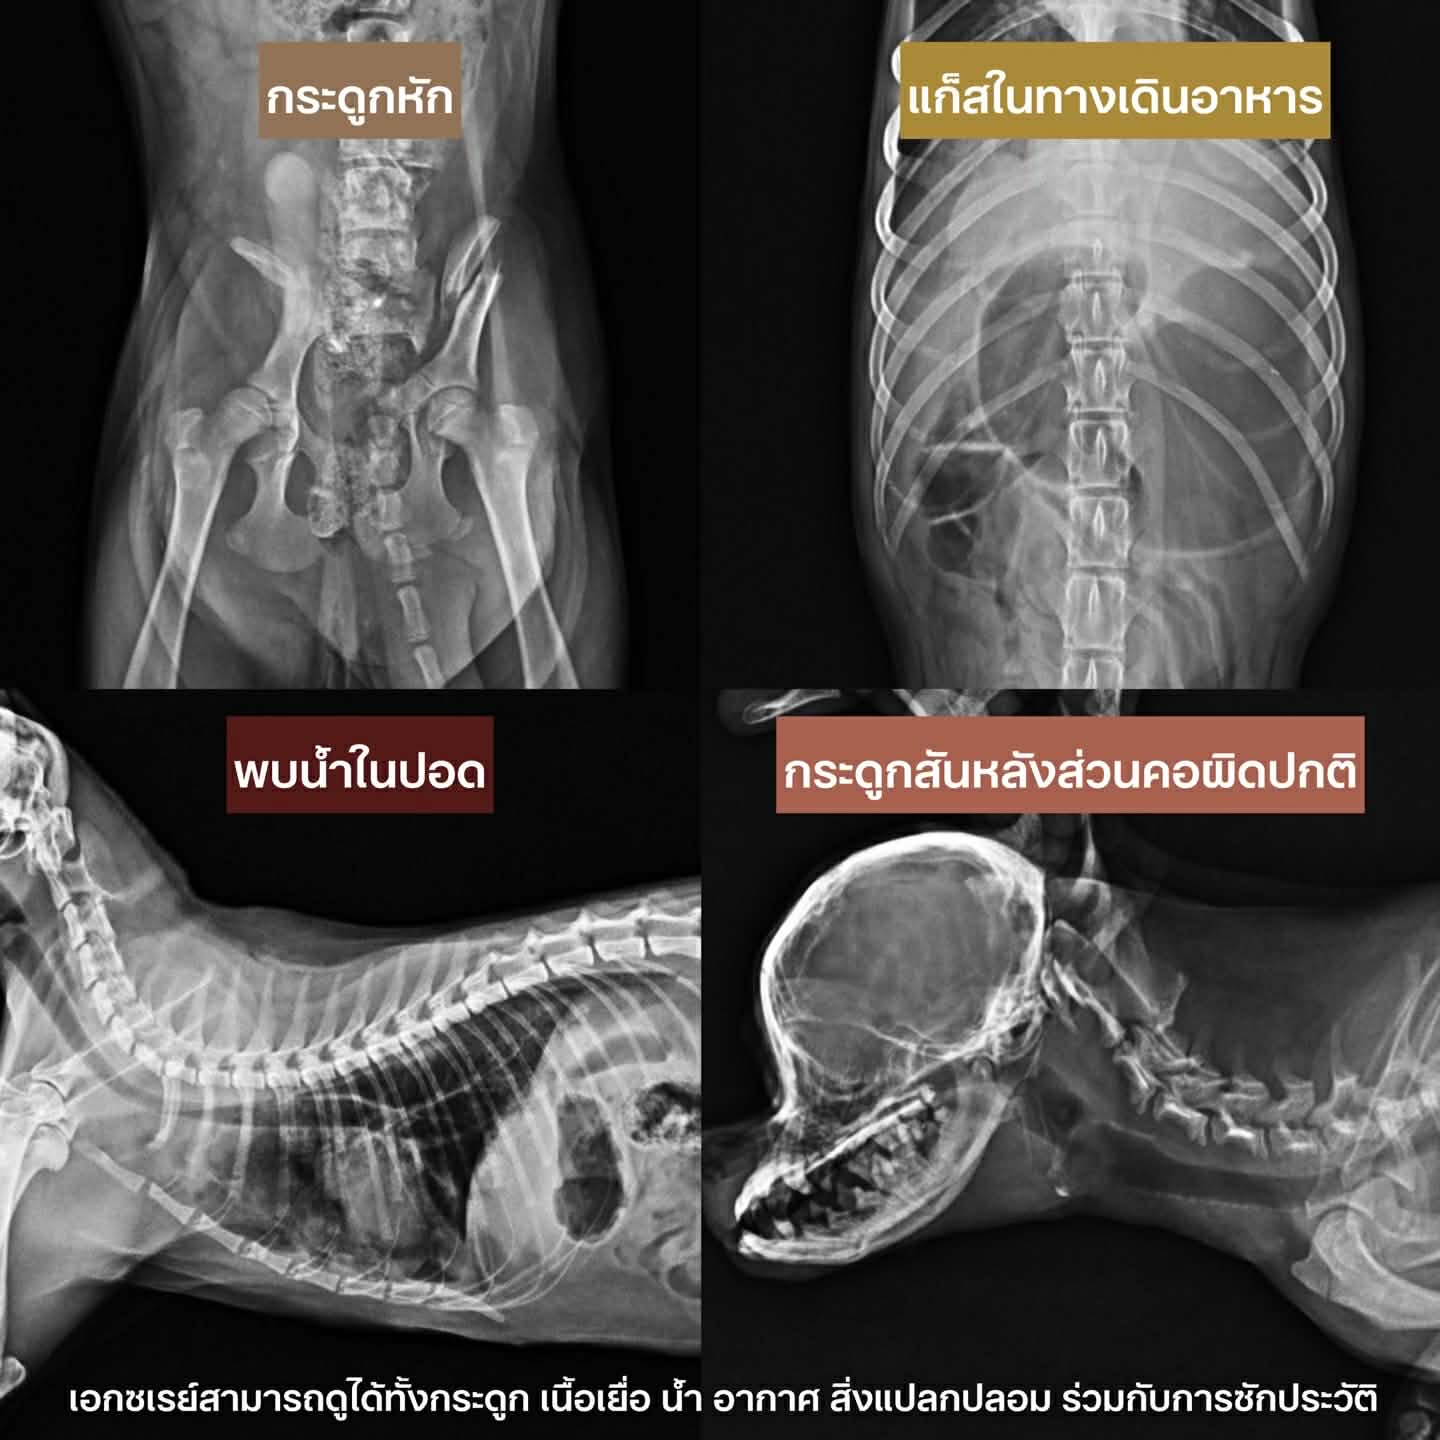

2. ประเมินการบาดเจ็บ: กรณีเกิดอุบัติเหตุ ช่วยให้เห็นโครงสร้างกระดูกที่หักหรือเคลื่อน เพื่อวางแผนผ่าตัดได้อย่างตรงจุด

3. เช็กระบบภายใน: ดูได้ทั้งแก๊สในทางเดินอาหาร สิ่งแปลกปลอมที่น้องเผลอกลืนลงไป หรือแม้แต่น้ำในปอด

รู้หรือไม่? เอกซเรย์สามารถบอกเราได้ทั้งเรื่อง กระดูก, เนื้อเยื่อ, น้ำ, อากาศ และสิ่งแปลกปลอม ร่วมกับการซักประวัติอย่างละเอียด